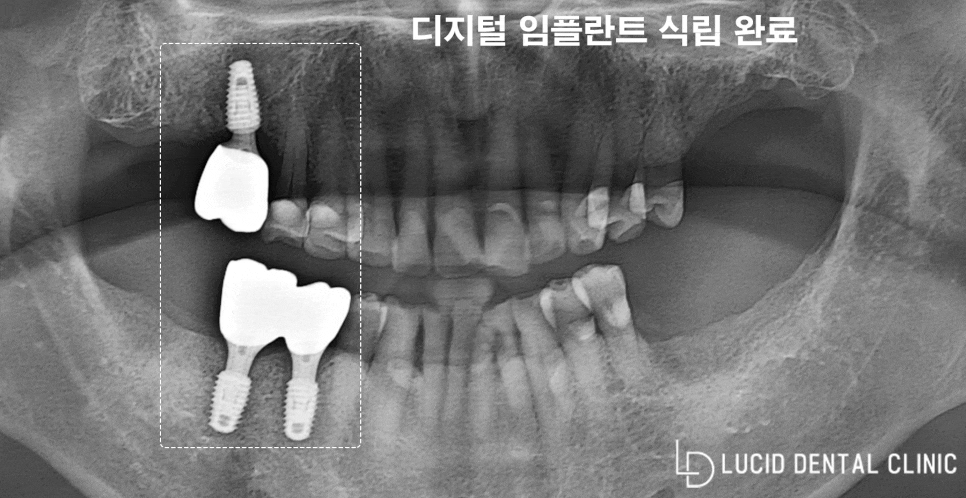

강남역 치과 임플란트 수술은

조금 정밀하게 이뤄지고 있는데요

미리 3D CT 사진을 촬영하여

환자의 구강 환경을 파악한 다음,

알맞은 식립 경로를 계산하여

임플란트 가이드 장치를 제작하고

치료 과정에 들어가고 있습니다.

미리 식립 경로를 파악하고 있으니

치료 기간이 단축될 뿐만 아니라

이후 나타날 수 있는 통증과 불편감을

최소화할 수 있다는 장점이 있죠.

임플란트 가이드 장치를 이용하여

계획된 위치 및 깊이에 맞게 식립을 마쳤고,

약 3개월 정도의 회복 시간을 가진 끝에

최종 보철을 장착하며 치료를 마무리했습니다.

임플란트 치료 전/후 비교샷